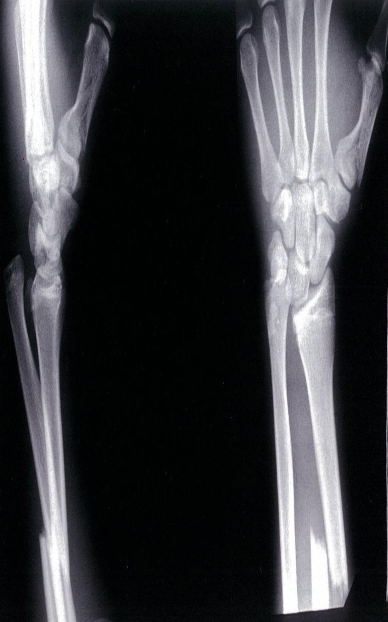

- Monteggia fracture-dislocation

- X-ray of the elbow (lateral view)

- Fracture of the proximal ulna with anterior dislocation of the head of the radius.

- Galeazzi fracture and fracture of the first metacarpal bone

- X-ray of the distal lower arm (left, lateral view; right, PA view)

- A distal third radius fracture and distal ulnar head dislocation can be seen; this fracture pattern is referred to as a Galeazzi fracture. Fracture of the first metacarpal bone